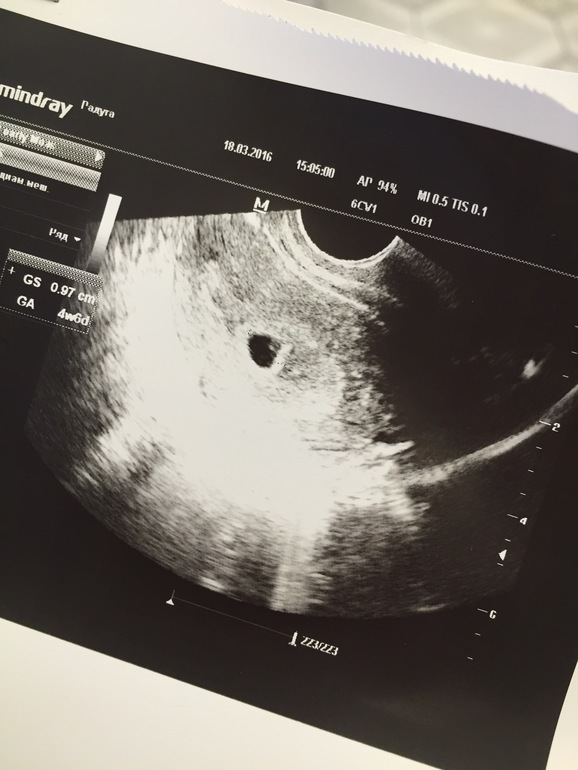

На 23дпо сходила на узи, срок по узи - 5 недель, пя 9,7мм, желточный мешочек 2,1мм, желтое тело 18мм. Эмбрион пока не видно, посмотрим и послушаем через две недели 💓 Заключение - развивающаяся маточная беременность раннего срока)